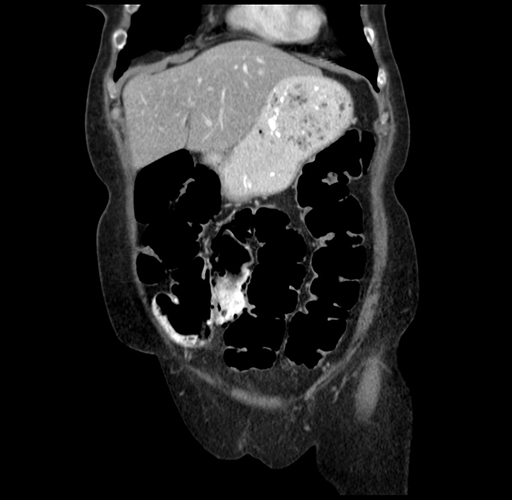

Pre-Chemo: Coronal Venous